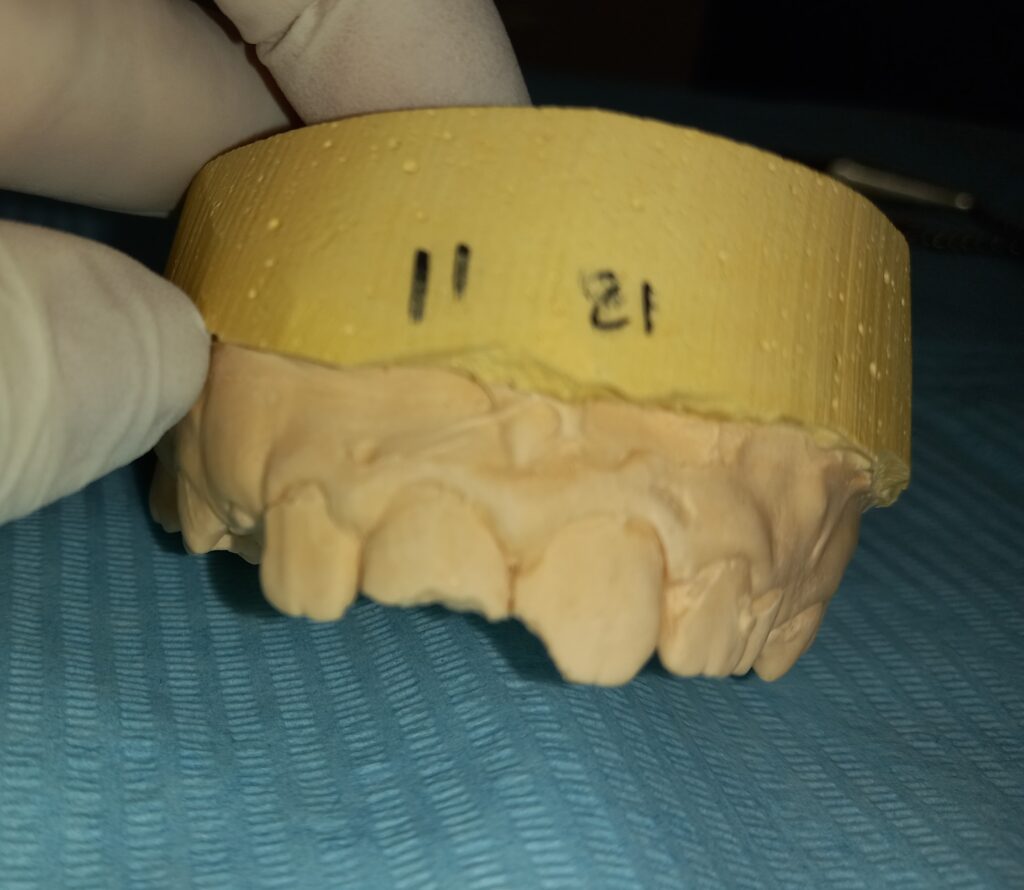

Ο μικρός ασθενής έσπασε στα πλαίσια του παιχνιδιού στο σχολείο τους δύο άνω κεντρικούς τομείς. Η αποκατάσταση πραγματοποιήθηκε με δύο αισθητικά λευκά σφραγίσματα από σύνθετη ρητίνη.

ΠΡΙΝ

Εκμαγείο αρχικής κατάστασης των σπασμένων δοντιών